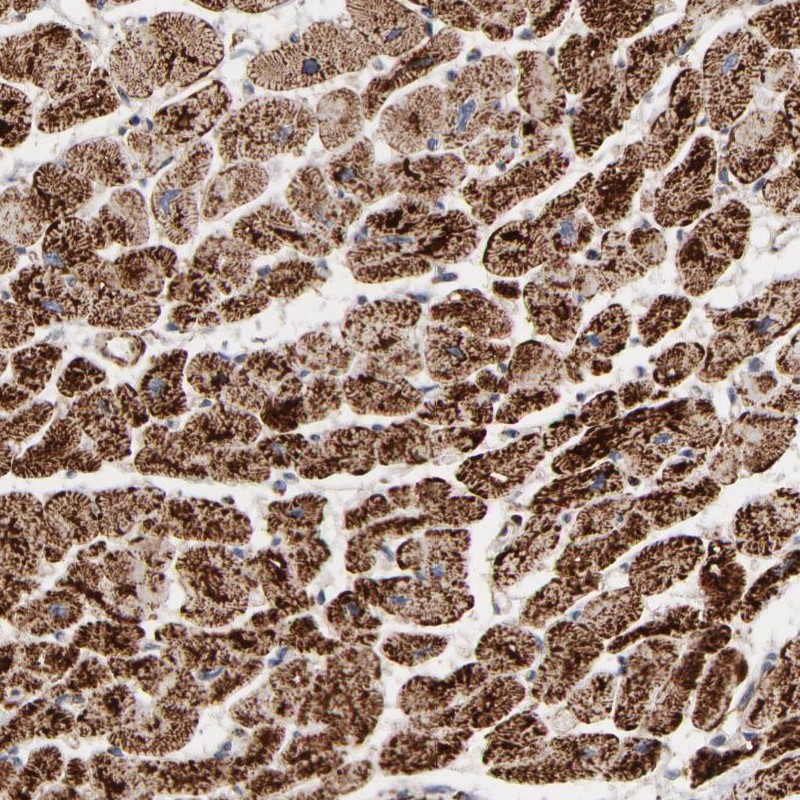

Immunohistochemistry analysis in human heart muscle and lymph node tissues using Anti-UQCRC1 antibody. Corresponding UQCRC1 RNA-seq data are presented for the same tissues.